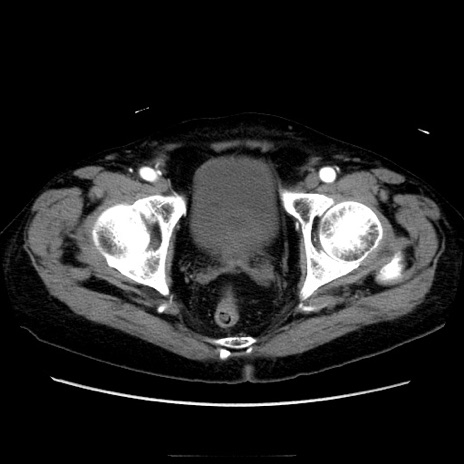

症例21(横断像)

【症例】70歳代男性

【主訴】腹痛

【現病歴】肝硬変・肝細胞癌にてかかりつけの方。約9時間前に食後より腹痛出現。症状が徐々に増悪し、嘔吐出現したため来院。

【既往歴】肝硬変、肝細胞癌(RFA、TACE後)

【身体所見】意識清明、表情苦悶様、BT 36℃、BP 129/78mmHg、P 88bpm、SpO2 97%(RA)、右上腹部から心窩部にかけて圧痛あり、反跳痛なし、筋性防御あり。

【データ】WBC 5800、CRP 0.16